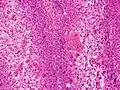

Adenoid squamous-cell carcinoma

Adenoid squamous-cell carcinoma Basaloid squamous-cell carcinoma

Basaloid squamous-cell carcinoma Clear-cell squamous-cell carcinoma

Clear-cell squamous-cell carcinoma Spindle-cell squamous-cell carcinoma

Spindle-cell squamous-cell carcinoma